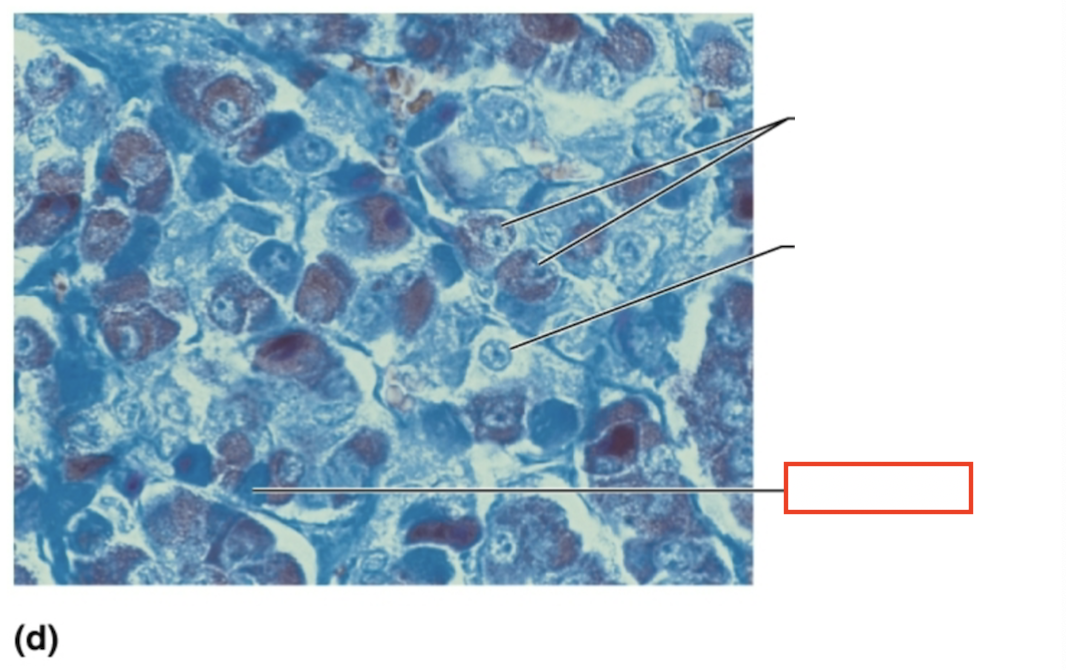

What structure is highlighted?

acidophils

What structure is highlighted?

chromophobe

What structure is highlighted?

basophil

What tissue is shown?

anterior pituitary